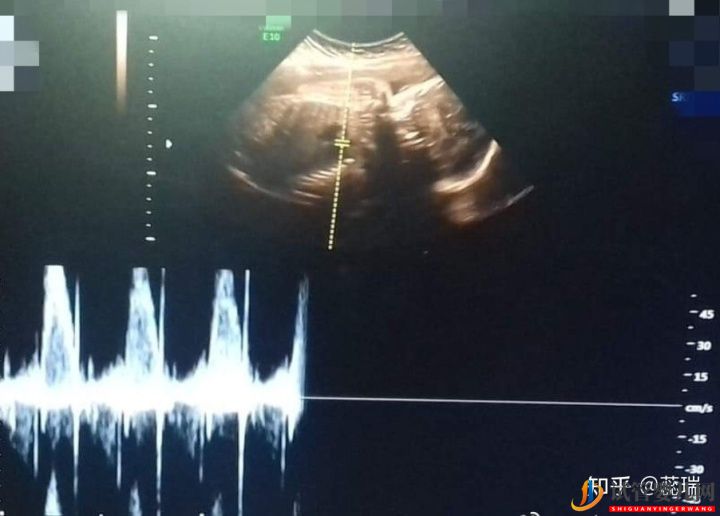

根據(jù)每人情況不同,用藥天數(shù)會不同,這期間通過驗血和陰道B超監(jiān)測卵泡發(fā)育情況,如果卵泡發(fā)育成熟,會打夜針,防止卵泡排出,把卵泡鎖住,固定卵泡,準備取卵,取卵同時男方取精,所以一般在打夜針之前男方應該儲存精子,(7天之內(nèi)的精子質量最好)